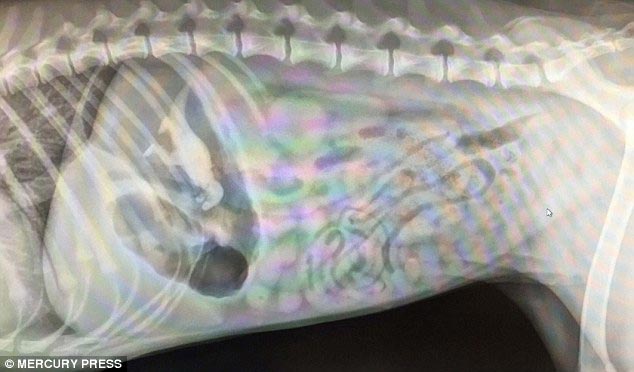

2 место - бездомный щенок лабрадора, который умудрился каким-то образом проглотить удочку

![Что на ужин? Рентгеновские снимки животных, с шокирующими предметами извлеченными из их желудков предметы извлеченные из желудков животных, рентгеновские снимки животных съевших предметы, необычные предметы съели животные]()

Вот она и сам щенок